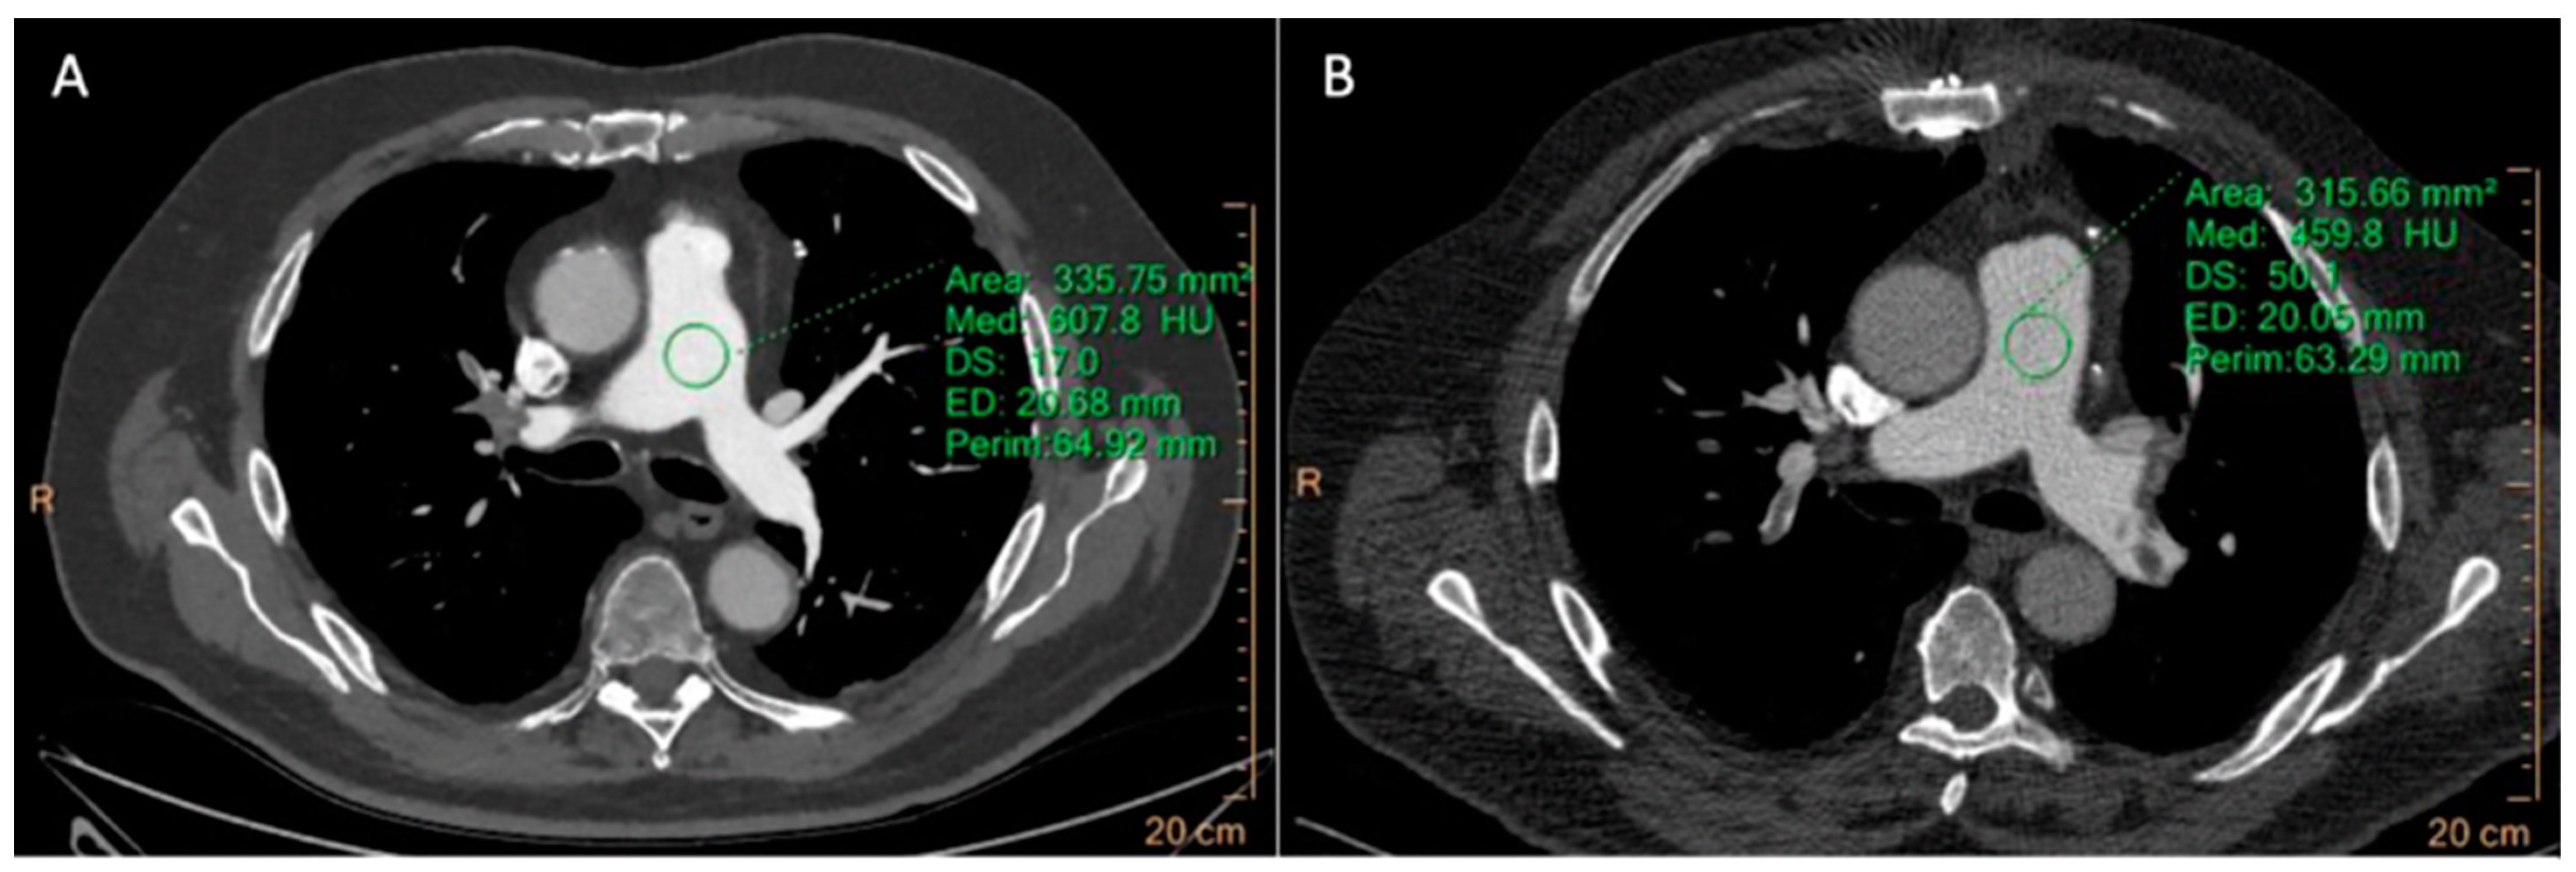

3.2.1. CCTA

| CCTA | LV | 591.97 ± 121.8 | 519.76 ± 117.52 | 0.001 | 15.77 ± 3.54 | 11.14 ± 5.33 | <0.001 | 19.61 ± 6.57 | 14.65 ± 8.44 | <0.001 |

| Aorta | 624.58 ± 117.8 | 489.33 ± 101.45 | <0.0001 | 16.73 ± 4.11 | 9.85 ± 7.15 | <0.0001 | 21.11 ± 6.9 | 13.77 ± 8.39 | <0.0001 | |

| LAD-prox | 619.77 ± 99.31 | 475.17 ± 105.21 | <0.0001 | 13.45 ± 6.71 | 7.79 ± 5.93 | <0.0001 | 20.28 ± 9.6 | 12.87 ± 10.4 | <0.0001 | |

| LCx-prox | 626.30 ± 82.54 | 434.89 ± 94.3 | <0.0001 | 13.84 ± 7.24 | 7.55 ± 6.24 | <0.0001 | 21.05 ± 7.61 | 10.85 ± 8.52 | <0.0001 | |

| RCA-prox | 618.53 ± 109.3 | 445.7 ± 78.56 | <0.0001 | 14.68 ± 7.25 | 8.22 ± 6.13 | <0.0001 | 22.36 ± 8.8 | 11.42 ± 9.19 | <0.0001 | |